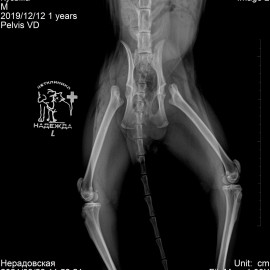

Через 2 месяца пришли с такими же симптомами относительно левой задней лапы (снимок 3). Была проведена операция (снимок 4).